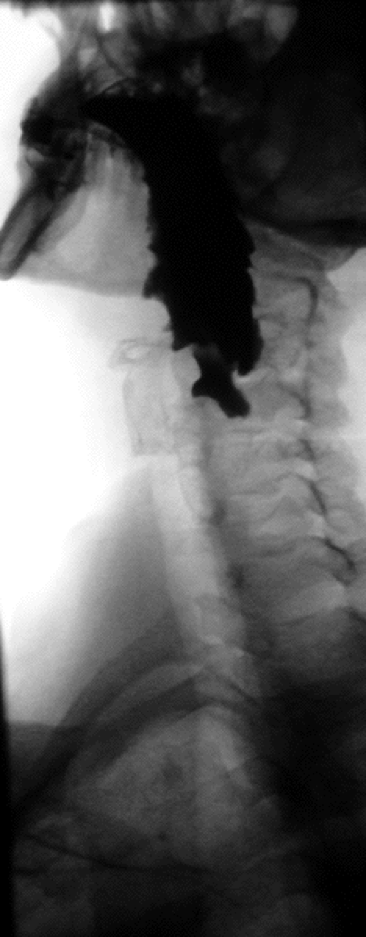

What are the anatomical and motor disorders of the esophagus?

Achalasia

What is Zenker’s Diverticulum?